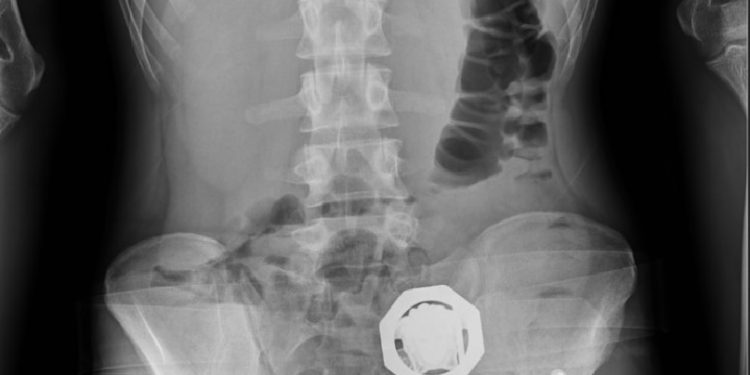

وتظهر الاشعة المقطعية للمتهمين داخل مصلحة الطب الشرعي وجود 33 حبة زنة 224 جران و40 حبة زنة 285 جرام و48 حبة زنة 840 داخل معدتهم.